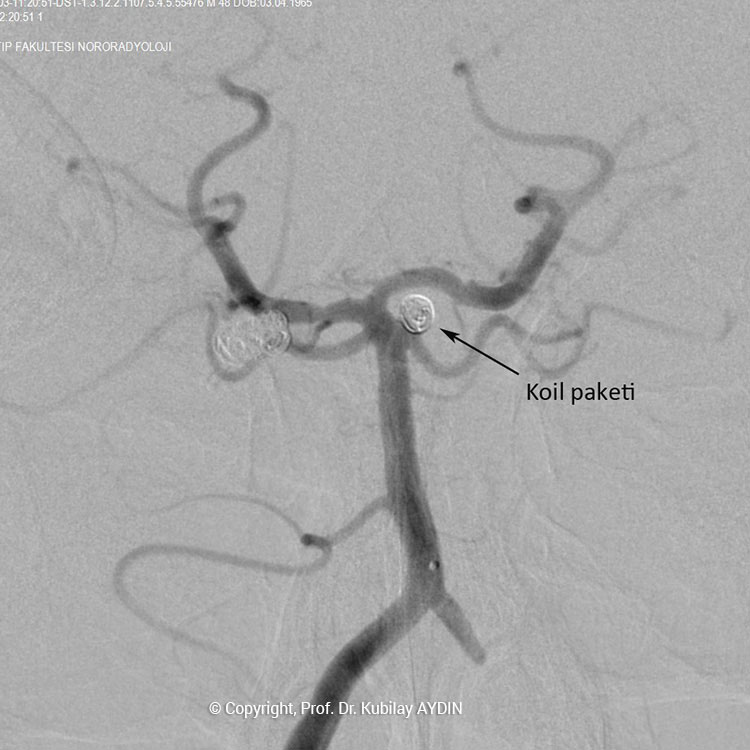

Geniş boyunlu anevrizmaların stent kullanılarak koillerle kapatılması işlemine “stent-yardımlı koilleme” adını veriyoruz. Bu işlemin ilk aşamasında anevrizmanın boynunu örtecek şekilde damar içine bir metal kafes (stent) yerleştirilerek, bir sonraki aşamada anevrizma kesesi içine konulan koillerin damar içine sarkması önlenir. Yani, burada stentin görevi, anevrizma içine doldurduğumuz koil adı verilen tellerin, damar içine sarkmasını önlemektir. Stent-yardımlı koilleme, geniş boyunlu anevrizmaların kapalı yöntemle tedavisinde tercih edilen bir yöntemdir.

Stent yardımlı koilleme tekniği ile anevrizma tedavisinde, anevrizmanın yerleştiği atardamar içerisine stent açılması için bir kateter yerleştirilir. Eş zamanlı olarak, anevrizma kesesi içerisine koilleme amaçlı farklı bir kateter yerleştilir. Damar içerisine bir stent açıldıktan sonra, anevrizma içerisideki kateterden gönderilen platinden yapılmış çok yumuşak yapıda koillerle anevrizma kesesi doldurulur. Stent, anevrizma içeriside bırakılan koillerin damar içine sarkmasına engel olur. Koilleme işlemine, anevrizma koillerle tamamen doldurulana ve anevrizma içine kan girmeyene kadar devam edilir.